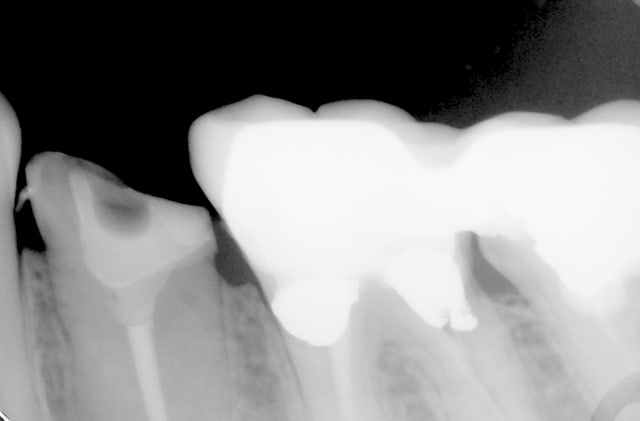

Voilà ce patient a consulté en Juillet pour une douleur à la mastication. Je regarde la radio, belle pêche sous les racines, en bouche, une fêlure traversant la dent dans le sens MD. A votre avis que faire dans ces cas et comment évaluez vous la réussite ou non de l'endo - CCC dans ces cas? Il n'avait aucune douleur quand j'appuyais transversalement de sur la moitié linguale ni sur la moitié vestibulaire (vers l'extérieur de la dent, pour "séparer" les dent).

Bref je fais l'endo, et lisant de plus en plus de choses sur le sans-tenon (surtout le risque de fracture supérieur qu'il engendrait par perte de substance dentinaire) je me suis lancé dans un "Nayyar" core, compo descendant dans les entrées canalaires et par dessus une CCC.

Ci-joint les radios.